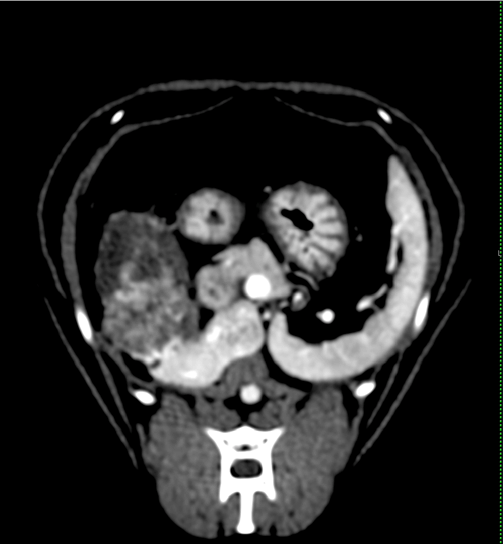

【実施症例】甲状腺癌に対する動注療法

ミニチュア・ダックスフンド、12歳、雌。

周囲組織に浸潤した甲状腺癌で外科的切除は困難であった。 大腿動脈からカテーテルを挿入し、腫瘍栄養血管である甲状腺動脈に抗がん剤と塞栓物質の選択的注入を行った。 実施後、腫瘍は縮小し症状の改善が得られた。

造影CT画像